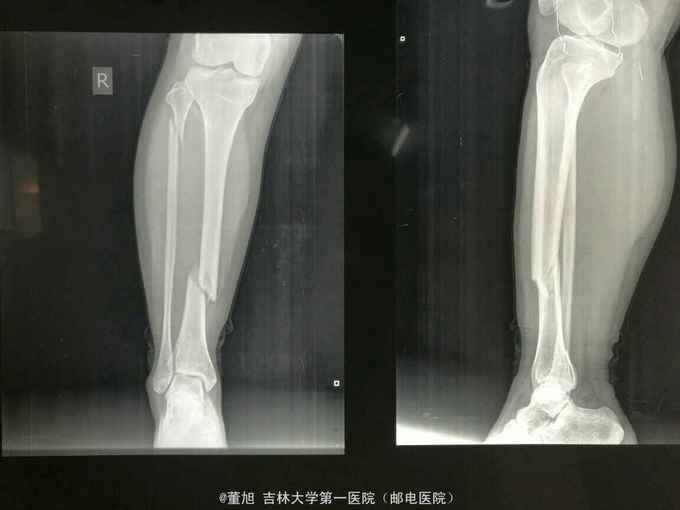

查体:右小腿肿胀畸形,中段压痛,可触及骨擦感及异常活动,下肢纵向叩击痛阳性,踝关节活动良好,肢端感觉良好,足背动脉可触及 辅助检查:右小腿正侧位提示胫骨中段骨折并可见游离骨块

诊断:右胫骨骨折 治疗:骨折切开复位外固定架固定术